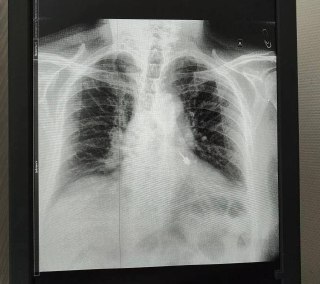

Во время приёма инструмент оказался в дыхательных путях мужчины. Он сразу почувствовал боль и отправился в больницу. Рентген показал, что бур находится в левом бронхе. Медики приняли решение экстренно прооперировать пациента, так как любое промедление могло привести к тяжёлым осложнениям, вплоть до летального исхода.

Врачам Мытищинской больницы предстояло выполнить ювелирную работу — при извлечении острая часть бура могла повредить стенки бронха и спровоцировать кровотечение. Поэтому действовать приходилось предельно точно. С помощью эндоскопа стоматологический инструмент зафиксировали и плавно извлекли, не травмировав ткани.